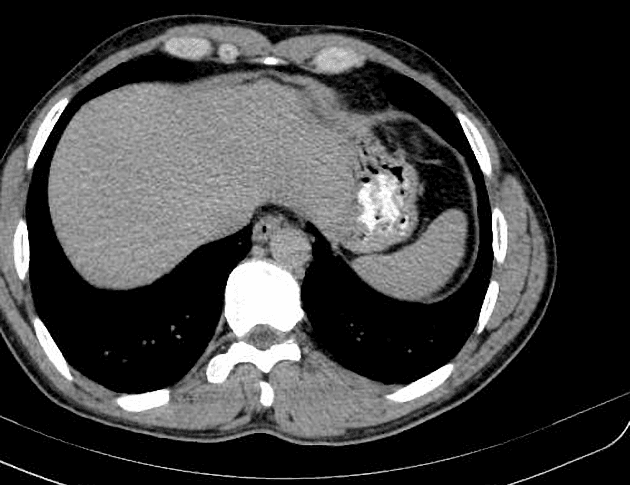

- Nhiều nang thận đơn thuần cũng như nhiều u thận tổn thương hỗn hợp đặc - nang.

- Tuyến tụy cũng chứa một số lượng rất lớn các nang rải rác khắp nơi.

Ca lâm sàng này biểu hiện đầy đủ các đặc điểm của hội chứng Von Hippel-Lindau (VHL), bao gồm nhiều nang thận đơn thuần và nhiều u thận tổn thương hỗn hợp đặc - nang. Tuyến tụy cũng có rất nhiều nang lan tỏa.